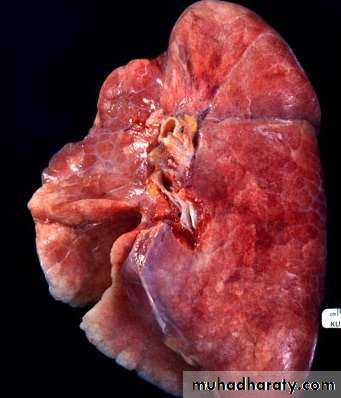

Lobar and bronchopneumonia

Lobar pneumonia’ is a radiological and pathological term referring to homogeneous consolidation of one or more lung lobes, often with associated pleural inflammation.

Bronchopneumonia’ refers to more patchy alveolar consolidation associated with bronchial and bronchiolar inflammation, often affecting both lower lobes.

The inflammatory response in lobar pneumonia

Evolves through stages ofCongestion.

Red hepatisation.

Grey hepatisation .

Finally resolution.

• Congestion

• Presence of a proteinaceous exudate—and often of bacteria—in the alveoli• RED HEPATIZATION

• Presence of erythrocytes in the cellular intraalveolar exudate• Neutrophils are also present

• Red Hepatization• GRAY HEPATIZATION

• No new erythrocytes are extravasating, and those• already present have been lysed and degraded

• Neutrophil is the predominant cell

• Fibrin deposition is abundant• Bacteria have disappeared

• Corresponds with successful containment of the

• infection and improvement in gas exchange